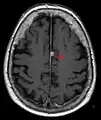

MRI of the brain and head has multiple diagnostic usages, including identifying aneurysms, strokes, tumors and other brain injury.[30] In many diseases, such as Parkinson's or Alzheimer's, MRI is useful to help differentially diagnose against other diseases.[31][32] On the topic of diagnosis, MRI data has been used with deep learning networks to identify brain tumors.[33]